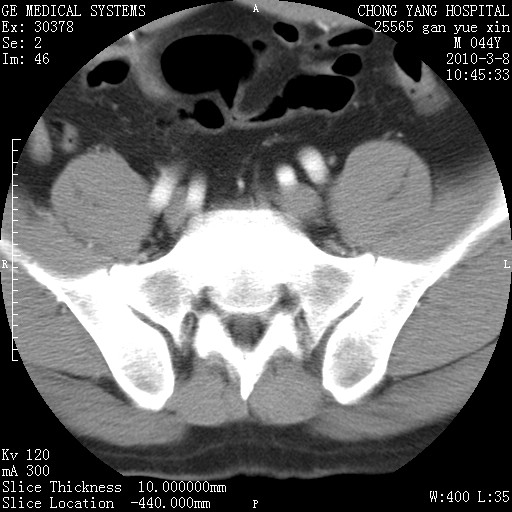

标题: CT24940:主动脉增强,典型病例。 [打印本页]

标题: CT24940:主动脉增强,典型病例。

夹层动脉瘤。

动脉夹层

夹层动脉瘤,典型

主动脉夹层。

动脉夹层的分型:

⒈debakey分型:根据主动脉夹层累及部位,分为三型:ⅰ型:原发破口位于升主动脉或主动脉弓部,夹层累及升主动脉、主动脉弓部、胸主动脉、腹主动脉大部或全部,少数可累及髂动脉。ⅱ型:原发破口位于升主动脉,夹层累及升主动脉,少数可累及部分主动脉弓。ⅲ型:原发破口位于左锁骨下动脉开口远端,根据夹层累及范围又分为ⅲa,ⅲb。ⅲa型:夹层累及胸主动脉。ⅲb型:夹层累及升主动脉、腹主动脉大部或全部。少数可累及髂动脉。

⒉stanford分型:a型:夹层累及升主动脉,无论远端范围如何。b型:夹层累及左锁骨下动脉开口以远的降主动脉。

夹层动脉瘤,少量胸水

夹层动脉瘤;左侧少量胸腔积液。

典型主动脉夹层。